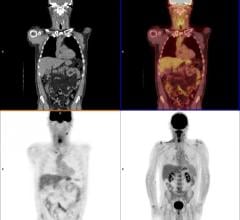

In the December featured basic science article in The Journal of Nuclear Medicine, Belgian researchers report on the first large-scale longitudinal imaging study to evaluate BACE1 inhibition with micro-PET (positron emission tomography) in mouse models of Alzheimer’s disease. PET imaging has been established as an excellent identifier of the amyloid plaque and tau tangles that characterize Alzheimer’s disease. Now it is proving to be an effective way to gauge treatment effectiveness.